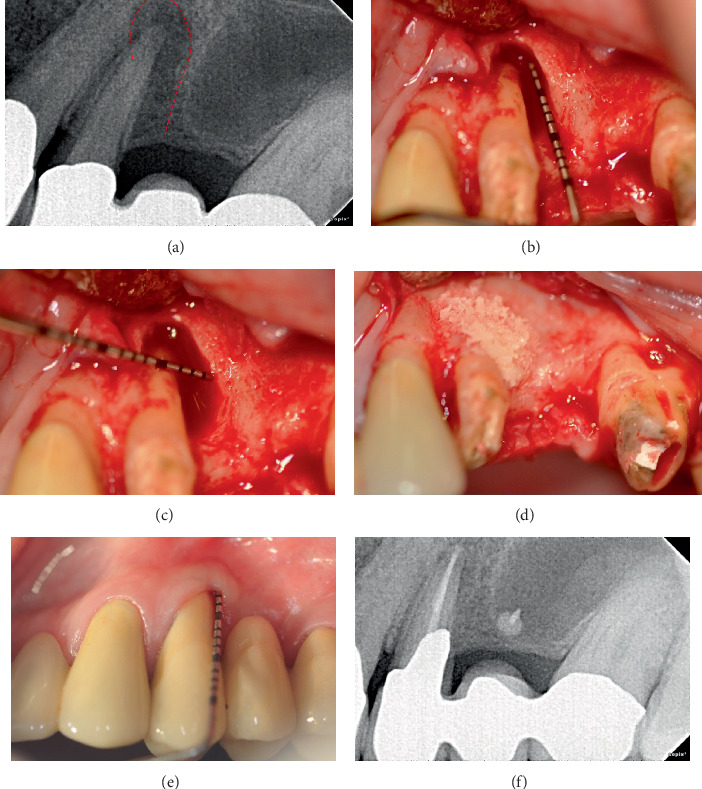

牙周再生(PR)可能是严重受损牙齿的一种可行的治疗选择。本病例系列通过长达13年的随访显示PR的长期益处。5例患者共6颗牙采用PR治疗骨内缺损。治疗方法包括提升粘骨膜瓣,根内固定,并用骨替代物填充骨缺损。PR后,探查深度(PD)明显减少(平均9.5±1.87 mm;p = 0.03),临床附着水平(CAL)也有统计学意义的增加(平均8.33±1.03 mm;P = 0.03)。x线片也证实了缺损部位骨缺损填充(平均9.67±2.25 mm;P = 0.03)。在长达13年的随访中,本病例系列表明,PR可减少PD,且牙龈萎缩最小,CAL增加,缺损部位骨填充,即使是复杂的牙周缺损延伸到根的根尖部分,这表明它是一种有效且可预测的治疗选择。

Periodontal regeneration (PR) could represent a viable treatment alternative for severely compromised teeth. This case series presents the long-term benefits of PR with up to 13 years of follow-up. A total of six teeth in five patients were treated for intrabony defects using PR. The treatment involved the elevation of a mucoperiosteal flap, root instrumentation, and filling the bony defect with bone substitutes. Following PR, a significant reduction in probing depth (PD) was observed (mean 9.5 ± 1.87 mm; p = 0.03) along with a statistically significant gain in clinical attachment level (CAL) (mean 8.33 ± 1.03 mm; p = 0.03). Radiographic bone defect fill at the defect site was also verified (mean 9.67 ± 2.25 mm; p = 0.03). This case series demonstrated that PR led to reduced PD with minimal gingival recession, gain in CAL, and bone fill at defect sites, even in complex periodontal defects extending to the apical portion of the root, over a follow-up period of up to 13 years, indicating it as an effective and predictable treatment alternative.